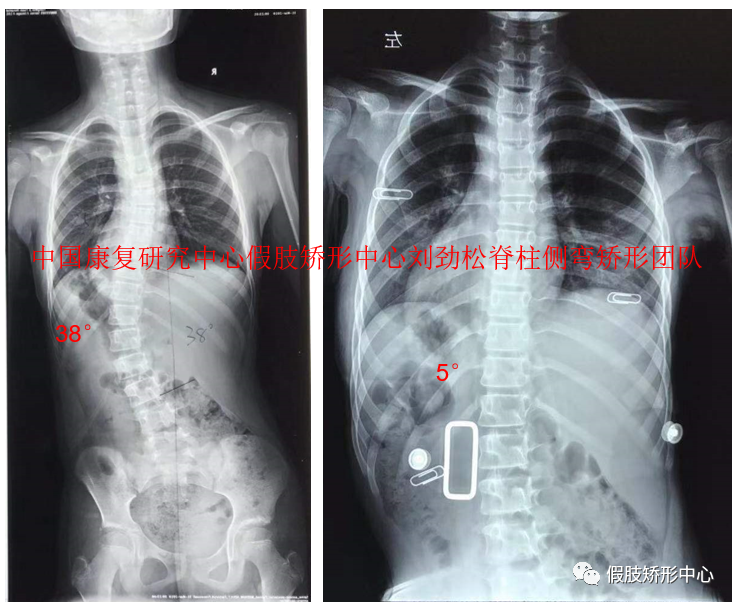

SCS脊柱側(cè)彎矯形器個案

SCS脊柱側(cè)彎矯形器3D雕刻